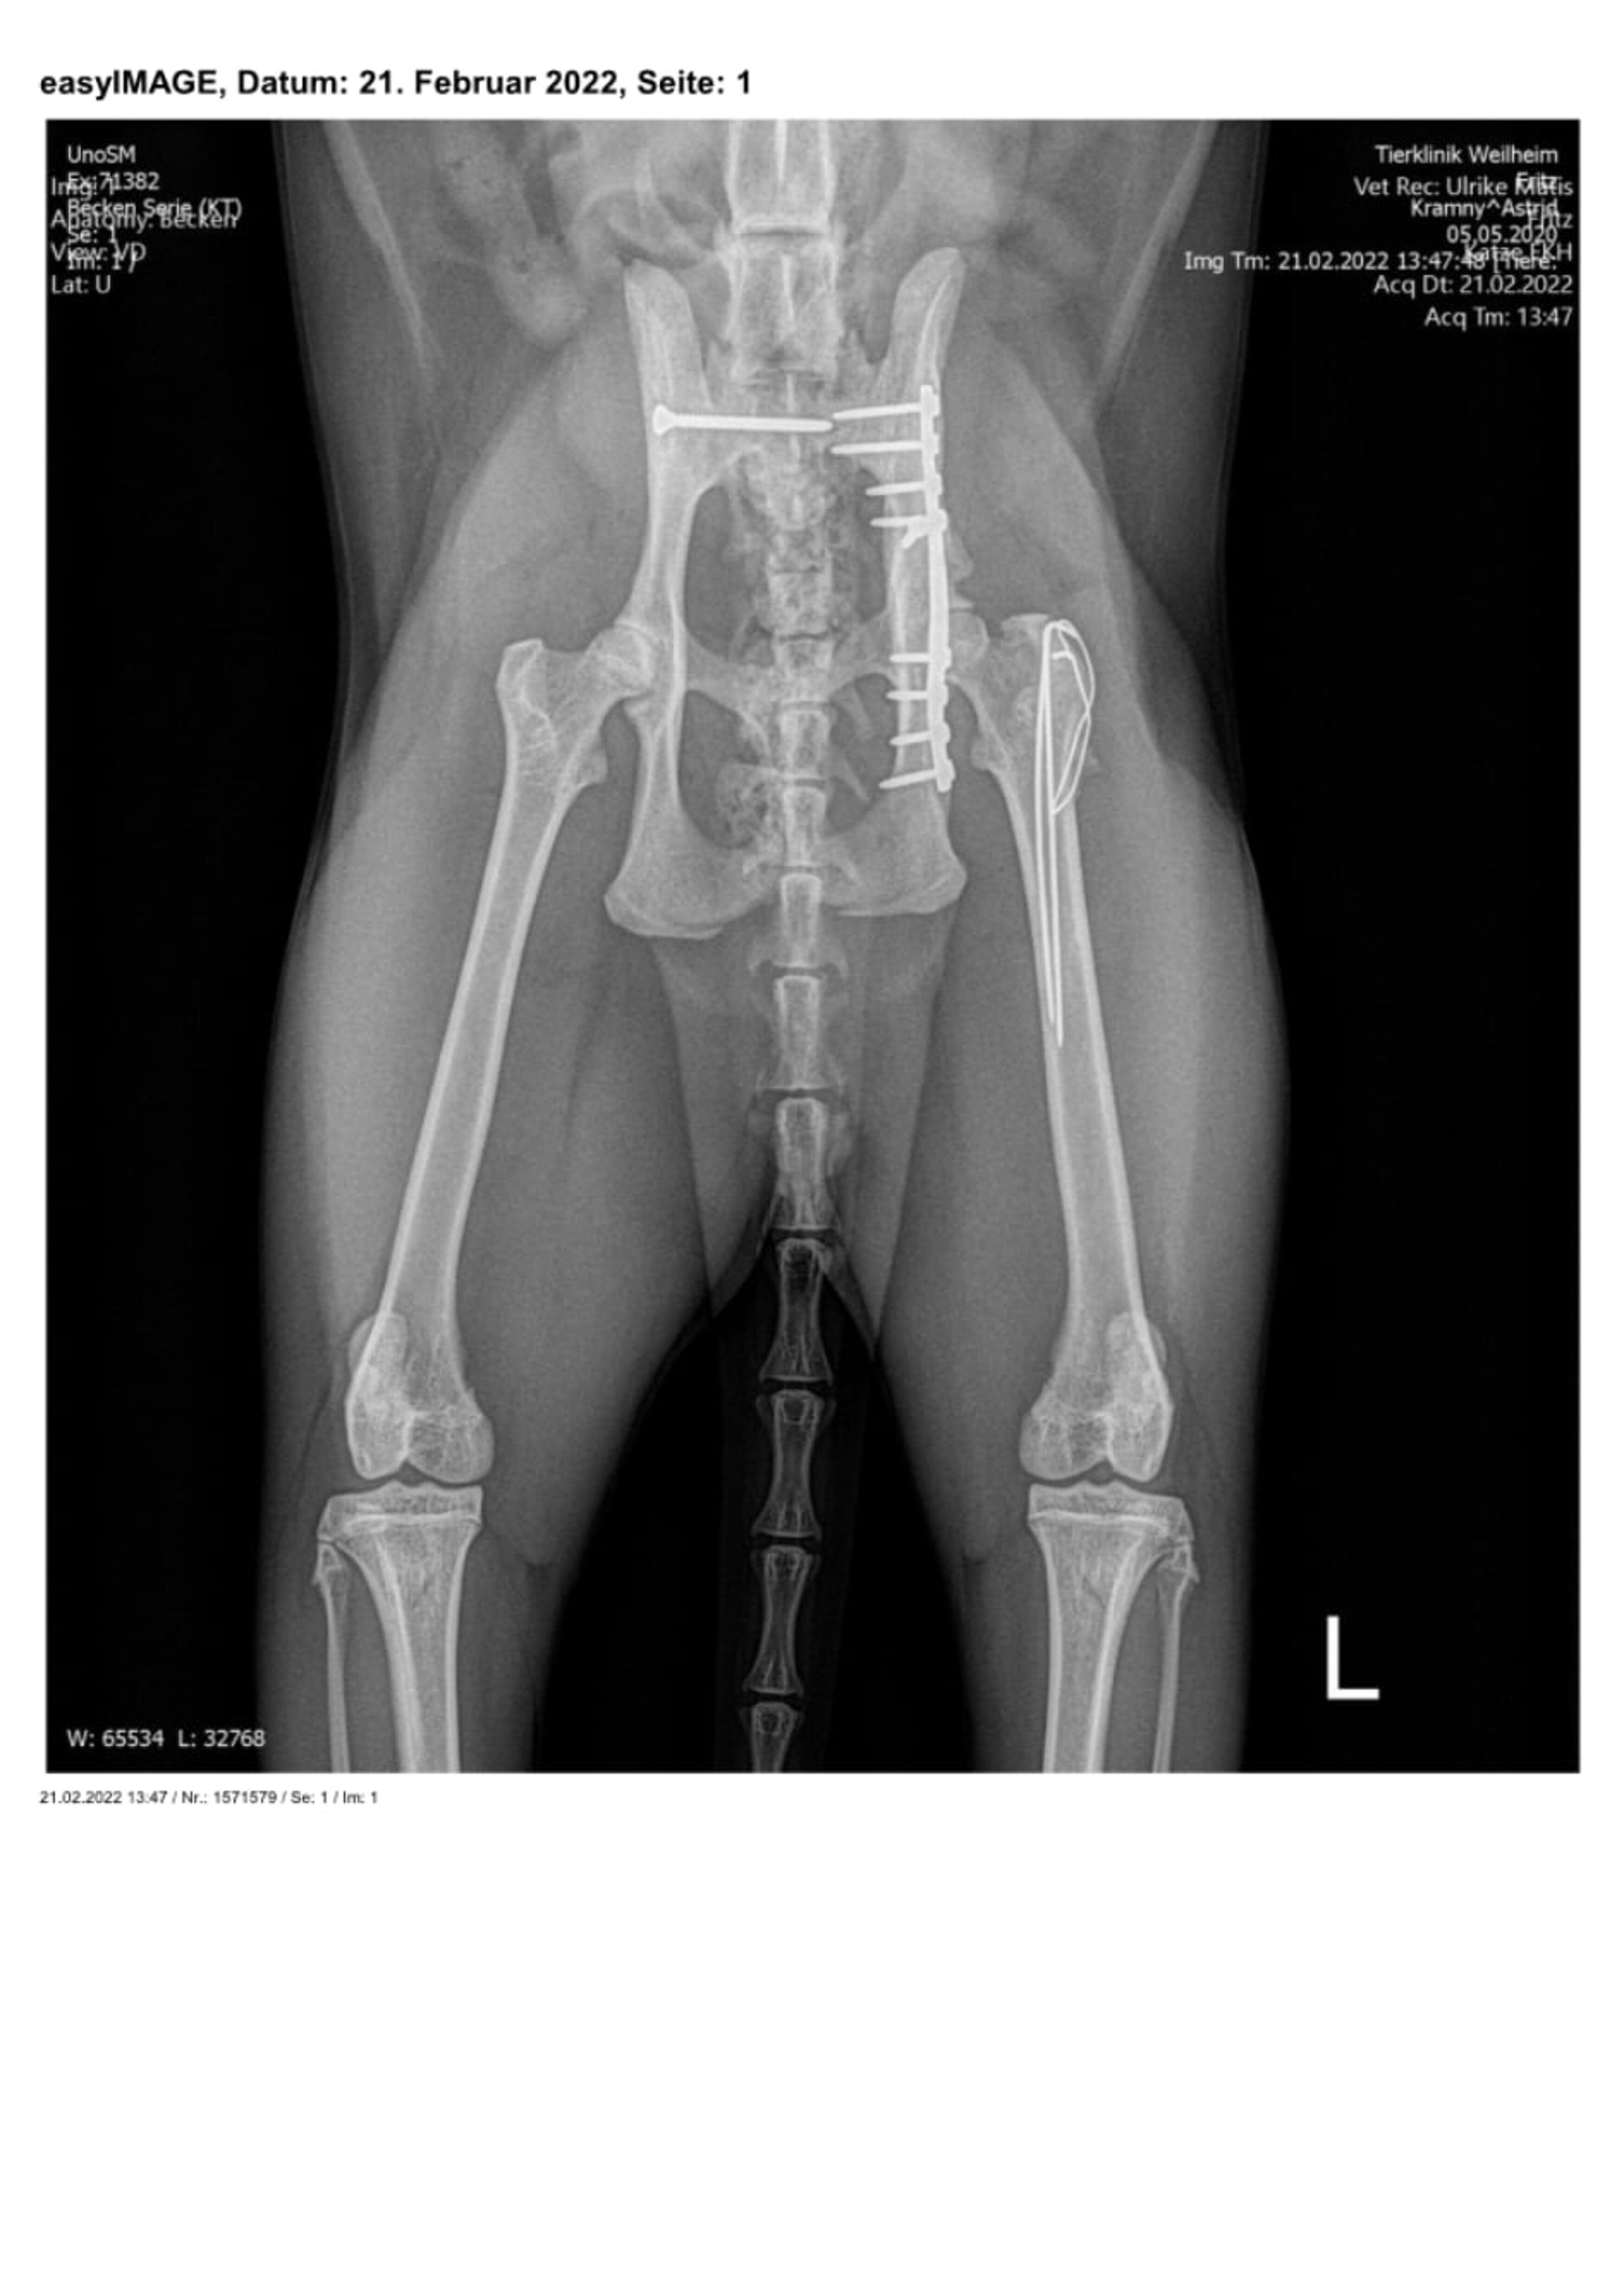

Zuerst wurden das ausgerenkte rechte Kreuz-Darmbein-Gelenk sowie der in seiner unmittelbaren Nachbarschaft verlaufende Ischias dargestellt und das Darmbein nach seiner Reposition mit einer 2,0 mm dicken und 24 mm langen Schraube an den Kreuzbeinkörper fixiert. Nach dem Wundverschluss wurde der Kater auf die andere Körperseite gelagert und sodann der direkt vor der Hüftgelenkspfanne Eine weitere Schraube diente der Adaptation eines Darmbeinsplitters an die Hauptfragmente. Da die Freilegung dieser Beckenregion meistens auch einen Knochenschnitt am Oberschenkel zum Verlagern der Kruppenmuskeln erfordert, wurden die Endsehnen dieser Muskeln mit dem knöchernen Segment abschließend durch 2 Bohrdrähte und einer 8-förmigen Drahtschlinge wiederbefestigt.

Röntgenbilder mit freundlicher Genehmigung Tierklinik Weilheim.

Bei der Nachuntersuchung des Patienten sechs Monate später präsentierte sich der Kater völlig beschwerdefrei und war sowohl in der Beckenregion als auch an den Gliedmaßen kräftig bemuskelt. Die Knochenbrüche waren sehr gut geheilt, ohne Einengung der Beckenhöhle und ohne die Ausbildung einer Hüftgelenksarthrose. Von einer Entfernung der Implantate wurde abgesehen, da alle Metallteile reizlos und ohne Lageveränderung integriert waren.